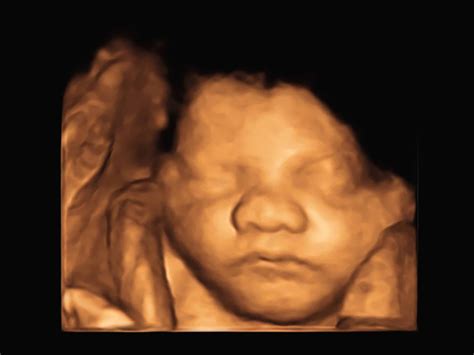

Down syndrome, also known as Trisomy 21, is a genetic condition caused by an extra copy of chromosome 21. While it cannot be diagnosed solely by looking at an image, certain physical features or markers can be identified during routine prenatal scans. When a sonographer or doctor talks about markers for Downs syndrome on ultrasound, they are referring to anatomical characteristics that are statistically more common in fetuses with this condition than in those without it.

• down syndrome 3d ultrasound pictures